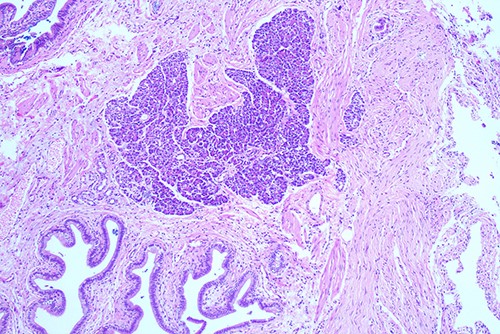

She proceeded to an elective laparoscopic cholecystectomy. At the time of her procedure, she was found to have features suggestive of chronic cholecystitis with peritoneal adhesions. Her procedure was straightforward and intraoperative cholangiogram showed a spiral cystic duct with the trifurcation of intrahepatic ducts. Her common bile duct appeared mildly dilated however tapered at the lower end and showed filling of the duodenum with no filling defects. The histology from the gallbladder showed variable fibromuscular thickening of the wall with intramural cystic Rokitansky-Aschoff sinuses, but no significant inflammation. Focal ectopic pancreatic acinar tissue (1 mm) within the gallbladder was found (Figs 1–3). There was no evidence of intestinal metaplasia, dysplasia or malignancy.

Histological examination of gallbladder ×40 showing island of ectopic pancreatic tissue adjacent to the mucosa of the gallbladder neck.